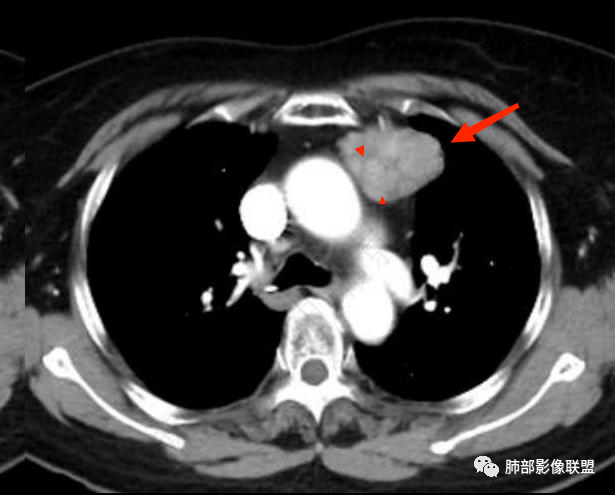

前上纵隔偏左侧实性病灶,边界清楚,边缘彭隆,浅分叶,内部密度均匀,未见钙化、脂肪密度,周围脂肪间隙清晰。

包膜完整,纤维分隔,结节感明显

平扫密度较均匀,增强渐进性不均匀强化,内见低密度纤维分隔。未见肿大淋巴结。未见胸腔积液。

肿块边界清楚,低密度纤维间隔,未见侵犯转移及增大淋巴结,多见于胸腺瘤AB型